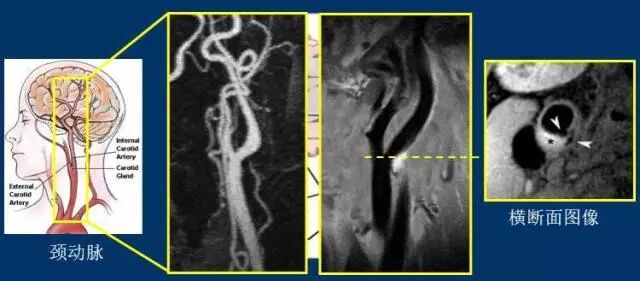

研究中心的张磊工程师对记者说,“在血管壁成像技术中,这些斑块以及脑动脉、颈动脉的管腔形态及其狭窄程度都能被看见,它是目前唯一能够无创、三维全景显示脑动脉和颈动脉血管壁、斑块,并分析斑块组成和破裂风险的手段。”单做血管造影无法诊断病人的具体病因,做血管壁成像却可以直接看到斑块和血栓。

(左边是现有技术下的血管造影结果,白色为血管。右边是血管壁成像技术拍出的结果,黑色的为血管。)

“通过血管造影结果看这位病人的血管是没有什么问题的,但在血管壁成像下可以看到,颈动脉分岔的地方有一个斑块,白色高亮部分。调取横断面图像可以看到,病人斑块旁有一个缺口,脱落的斑块从缺口跑出来,形成血栓,堵塞血管。”